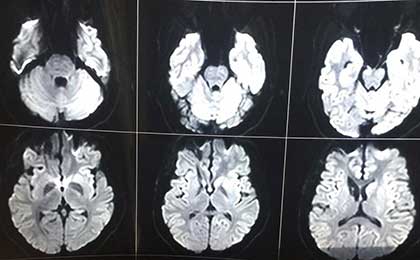

frontal epidermoid pre diffusion

• frontal epidermoid pre diffusion